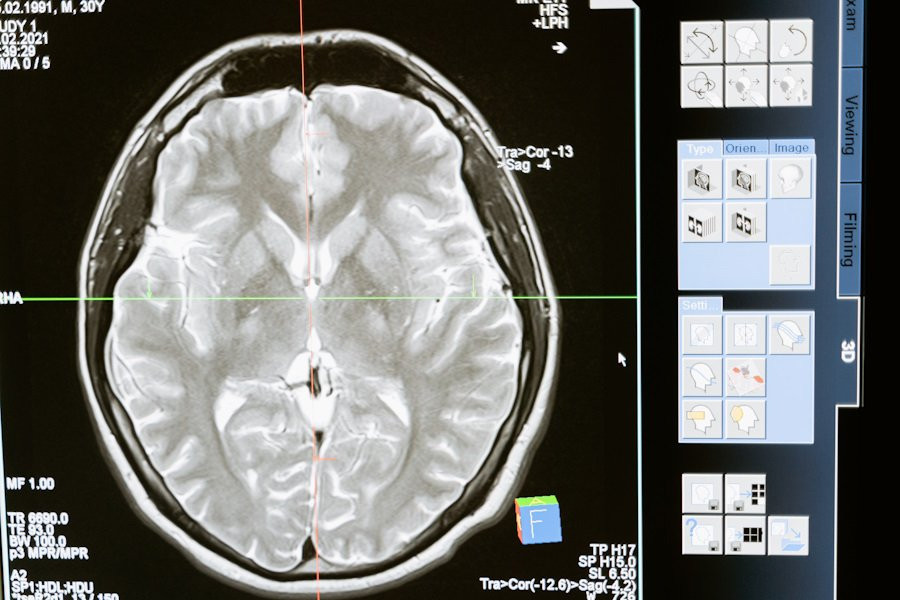

Ученые отрицают, что полушарие мозга контролирует противоположную часть тела

Ученые из Pennsylvania State University опровергли устоявшееся мнение о том, что каждое полушарие мозга контролирует противоположную часть тела. Результаты их исследования, опубликованные на портале Journal of Physiology, могут изменить подходы к реабилитации пациентов после инсульта.

Новая модель, называемая гипотезой комплементарного доминирования, показывает, что оба полушария мозга вносят свой вклад в управление движениями. Доминирующее полушарие отвечает за плавные и эффективные движения, тогда как недоминантное полушарие контролирует устойчивость и сопротивление неожиданным условиям.

Эти открытия предполагают, что повреждения одного полушария мозга могут вызвать специфические нарушения не только в противоположной руке, но и в руке на той же стороне повреждения. Новое вмешательство, разработанное учеными, помогает уменьшить эти дефициты и улучшить функциональную независимость у пациентов после инсульта.